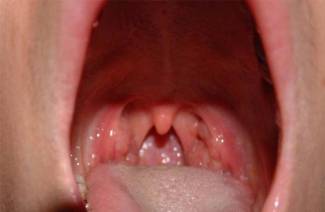

La laringotraqueitis se confirma sobre la base de quejas e historial del paciente, resultados de exámenes y estudios de laboratorio e instrumentales. En el examen visual inicial del paciente, puede ver que la laringe tiene un color rojo brillante, hiperemia de los tejidos, exudado purulento (placa) visible en la luz, la membrana mucosa está engrosada e hinchada. En la forma aguda de la enfermedad, tiene un color azulado y hemorragias de punto pequeño en la capa submucosa. Los siguientes estudios ayudan a diagnosticar la laringotraqueitis: